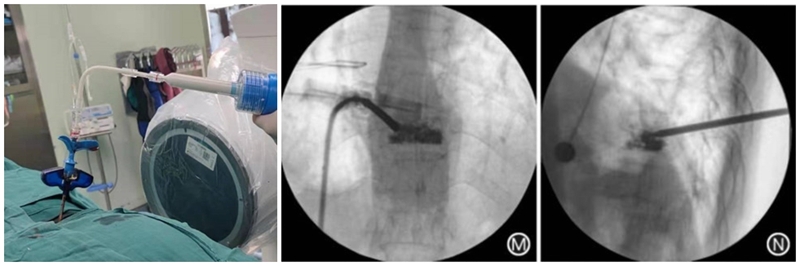

患者女,73岁,摔伤致T10椎体压缩骨折,伤后3d行PCKP治疗。

(1)定位与穿刺:透视下确定伤椎椎弓根外缘上1/3 入路点及伤椎上终板或下终板方向并做好标记。由于穿刺容错率高,穿刺针(4. 2 mm)不用过度内倾,不必苛求针尖在椎体内侧壁、后壁位置,穿刺针从椎弓根外缘沿椎弓根方向缓慢穿刺入椎体即可,针尖务必穿刺入椎体后1/3。

(2)弯角导丝开腔:弯角骨钻开腔器械刺入椎体时,注意开腔工具手柄与伤椎终板平行,不要强行开腔,多透视侧位,否则弯导丝可能穿破终板,导致医源性骨水泥渗漏。C形臂X线机正位透视下,导丝到达椎体对侧椎弓根处即可。

(3)弯角骨钻扩张:C形臂X线机正位透视下,弯角骨钻开腔器械螺旋手柄顺时针扭转,让弯角骨钻沿导丝前进开路,将椎体内部钻出弧形通道。操作中注意骨钻沿导丝旋进旋出要完全,旋进不够,后期球囊无法到达对侧,旋出不完全,骨钻会卡在工作套筒上无法拔出。

(4)置入球囊:插入带导丝弯角球囊时注意透视球囊方向,反复调整务必与终板平行。如需要拔出球囊调整方向,务必先拔导丝再拔球囊,透视球囊标记点必须完全从工作套管内出来,否则易造成弯角球囊与工作套管边缘卡磨破裂。

(5)扩张球囊:注入造影剂扩张球囊过程中,注意观察术中正侧位透视图像,控制压力值,不必苛求球囊顶到上下终板,以免发生医源性终板破裂,造成椎间隙骨水泥渗漏可能。注意弯角球囊扩张完毕后拔除顺序:先拔导丝再拔球囊。

(6)注入骨水泥:应用骨水泥灌注管灌注骨水泥时,由聚醚醚酮树脂制成的灌注管在骨水泥灌注完成后要及时拔除,避免椎体内骨水泥硬化后无法拔出;椎体穿刺侧骨水泥灌注不满意,可拔除输送套管,直接连接穿刺套管,进行二次灌注。

术后行影像学检查,显示骨水泥弥散满意,达到了单侧穿刺,双侧弥散的效果,无渗漏